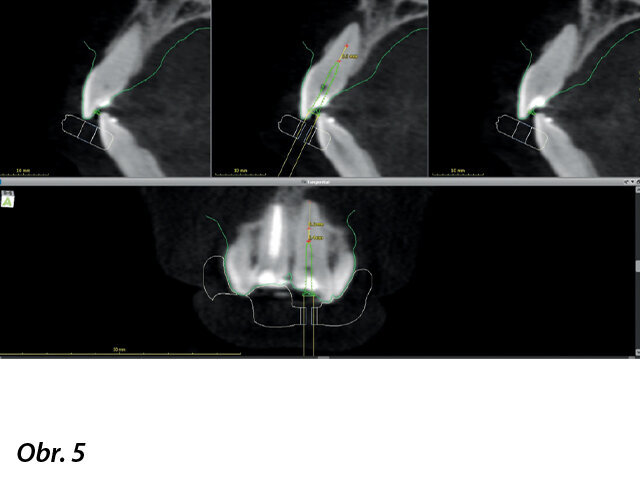

Byly zhotoveny silikonové otisky a vytvořen sádrový zubní model, který byl naskenován (iTero, Align Technology) (obr. 4). CBCT zobrazení i skeny modelů byly vyrovnány a zpracovány pomocí coDiagnostiX. Virtuální kopie vrtáčku s průměrem 1,2 mm a délkou 17 mm (Meisinger) byla vložena do skenů v pozici, která umožnila přístup do identifikovaného systému kořenových kanálků v apikální třetině zubu (obr. 5). Pozice vrtáčku byla zkontrolována ve 3D. Dále byla 3D šablona exportována jako STL soubor a odeslána do 3D tiskárny (Form 2, Formlabs) (obr. 6–9).